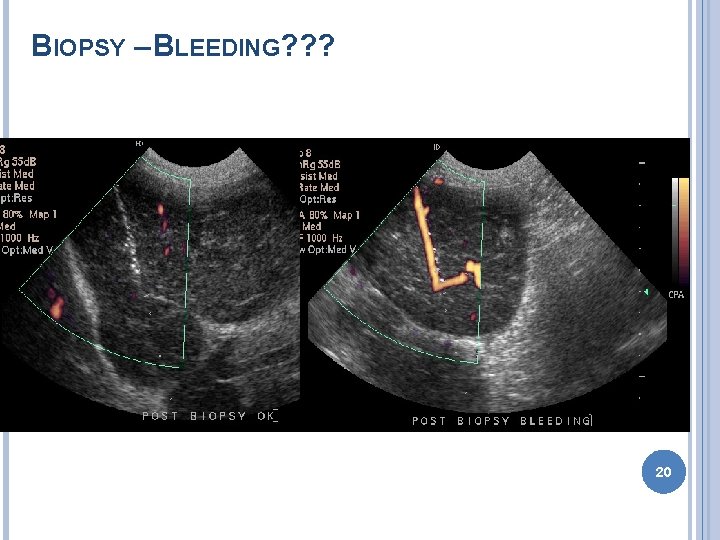

BIOPSY – BLEEDING? ? ? 20